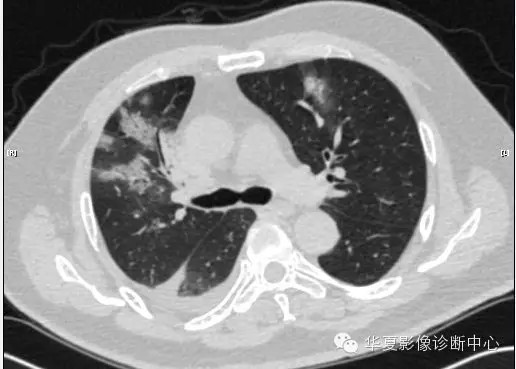

【病例学习】甲型H7N9禽流感一例

男性 63

发热咳嗽5天

2013-4-5拍片示右肺实变,收入院,追问病史,发病期间肌肉酸痛,头痛,无腹痛腹泻,无明显胸闷气急,无意识改变。有高血压病史,无其它病史。

2013-4-7CT进一步检查。

最终诊断:H7N9。